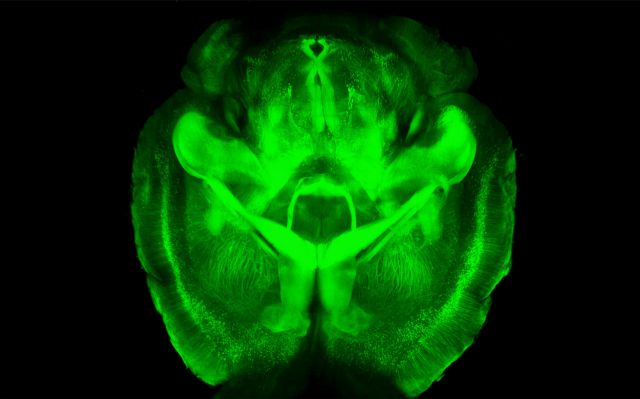

Δεν είναι η πρώτη φορά που επιστήμονες προσπαθούν να δημιουργήσουν διάφανους ιστούς και όργανα, αλλά τώρα τα αποτελέσματα είναι «συνταρακτικά».

Νευροχειρουργοί και χημικοί μηχανικοί από το Πανεπιστήμιο του Στάνφορντ συνεργάστηκαν για να αναπτύξουν μία διαδικασία που καθιστά διάφανο τον εγκέφαλο ποντικών.

Με τον τρόπο αυτό και με ειδικές χρώσεις, μπορούν να δουν για πρώτη φορά λεπτομέρειες στις εσωτερικές δομές, αφήνοντας ανέπαφη την ύλη του εγκεφάλου, καθώς μέχρι τώρα για να μελετήσουν τις δομές θα έπρεπε να πάρουν λεπτές τομές του εγκεφάλου με λέιζερ.

Όπως σχολίασαν ειδικοί «είναι ένα νέο εργαλείο που δεν χάνεις ίχνος λεπτομέρειας».

Παρόλο που η μέθοδος προς το παρόν αναπτύχθηκε μόνο σε εγκεφάλους ποντικών, η ομάδα εκτίμα πώς μπορεί να εφαρμοστεί και στον ανθρώπινο εγκέφαλο, αλλά όχι σε ζωντανούς. Παράλληλα, αναμένεται να χρησιμοποιηθεί και σε εργαστήρια που βιοψίες σε όγκους.

Η έρευνα δημοσιεύτηκε στην Online έκδοση της επιστημονική επιθεώρησης Nature.